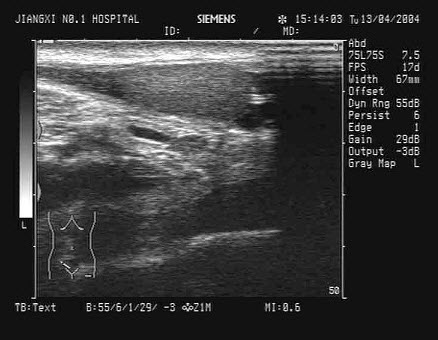

16、单项选择题

男,63岁,因左侧腰部疼痛不适伴无痛血尿1月余就诊,B超显示左肾集合系统分离3.9cm,如图所示,最可能的诊断为()

A.左输尿管结石

B.左输尿管癌

C.左输尿管炎性狭窄

D.左输尿管畸形

E.左输尿管血块